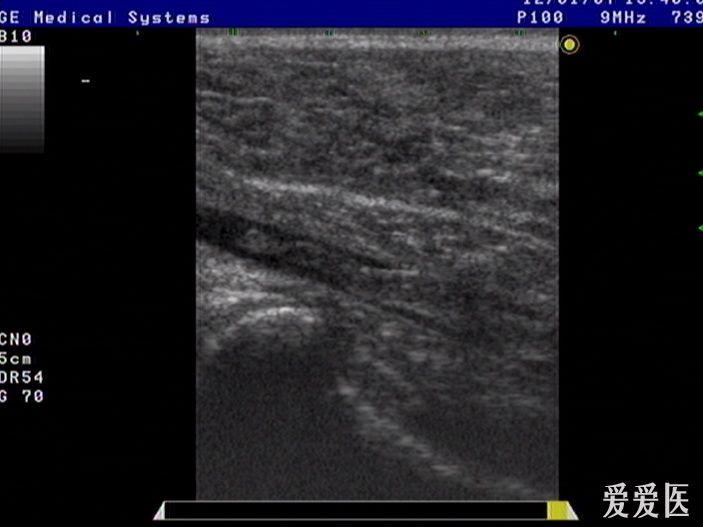

胫后静脉栓塞 - 超声医学讨论版 - 爱爱医医学论坛

一位63的老人因右小腿肿胀疼痛行走不便来医院超声检查的图像,股静脉